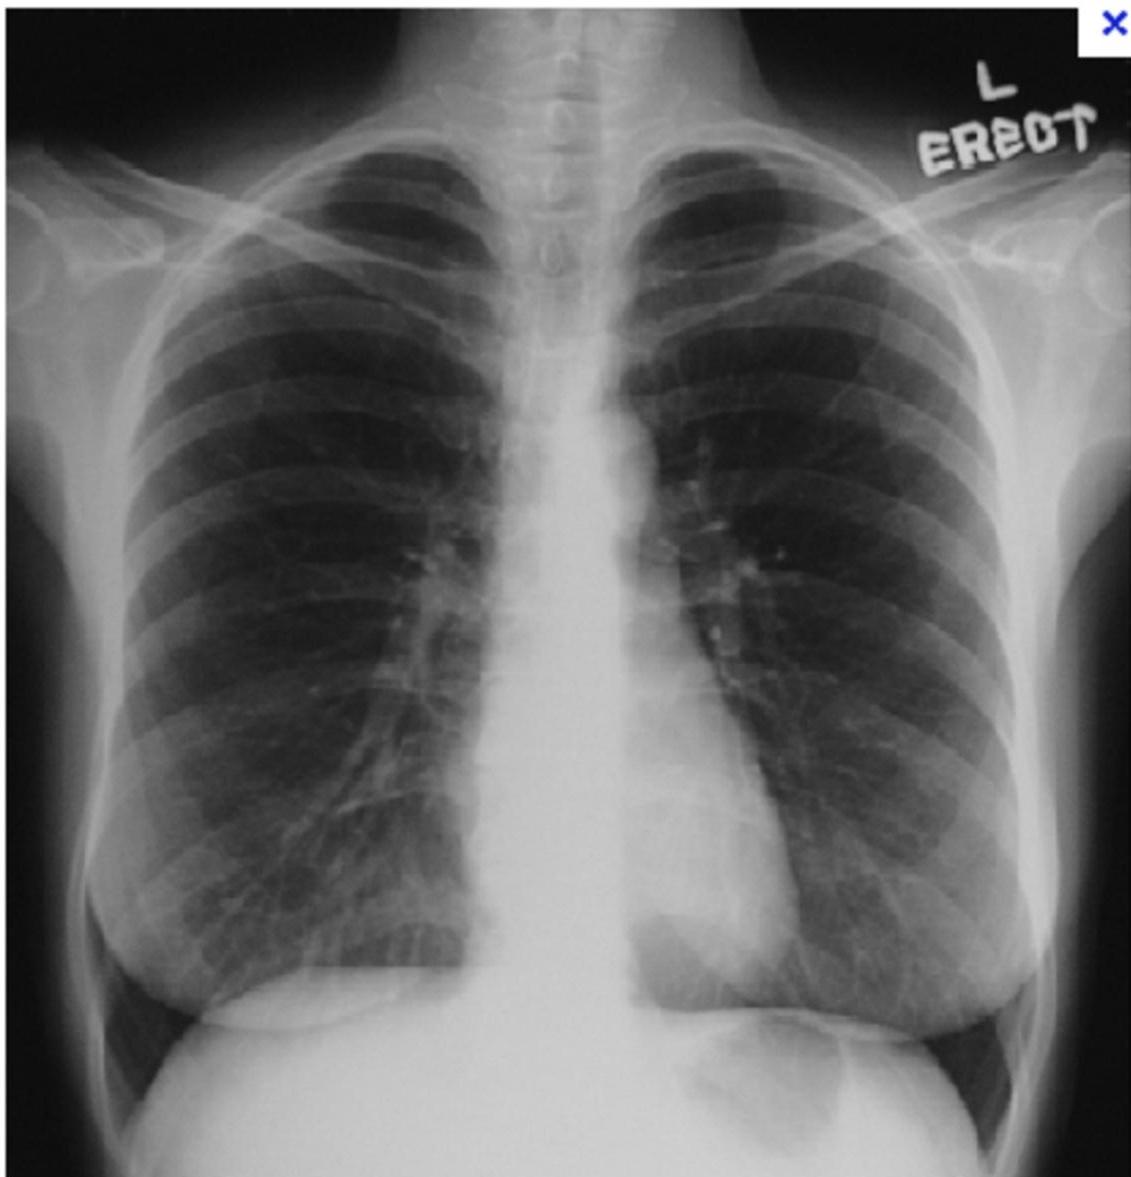

Case 1: Pulmonary Embolism (PE)

- Presentation: 62F, 3 weeks post-right THA, admitted for COPD exacerbation. Sudden onset L-sided chest pain (8/10), pleuritic, O2 sat drop (94% â 88% on 2L NC).

- Vitals: Afebrile, HR 120, BP 110/70, RR 28.

- Exam: Accessory muscle use, EAE, loud S2.

- Labs: Positive D-dimer, Troponin 0.12 (Normal < 0.04), BNP 520.

PE

- CXR Findings:

- Westermark sign: Clarified area (hyperlucency) secondary to oligemia.

- Hampton sign: âDome stuffedâ (hump).

- Management Plan: Give heparin (âheforinâ [sic]) and send to CT.